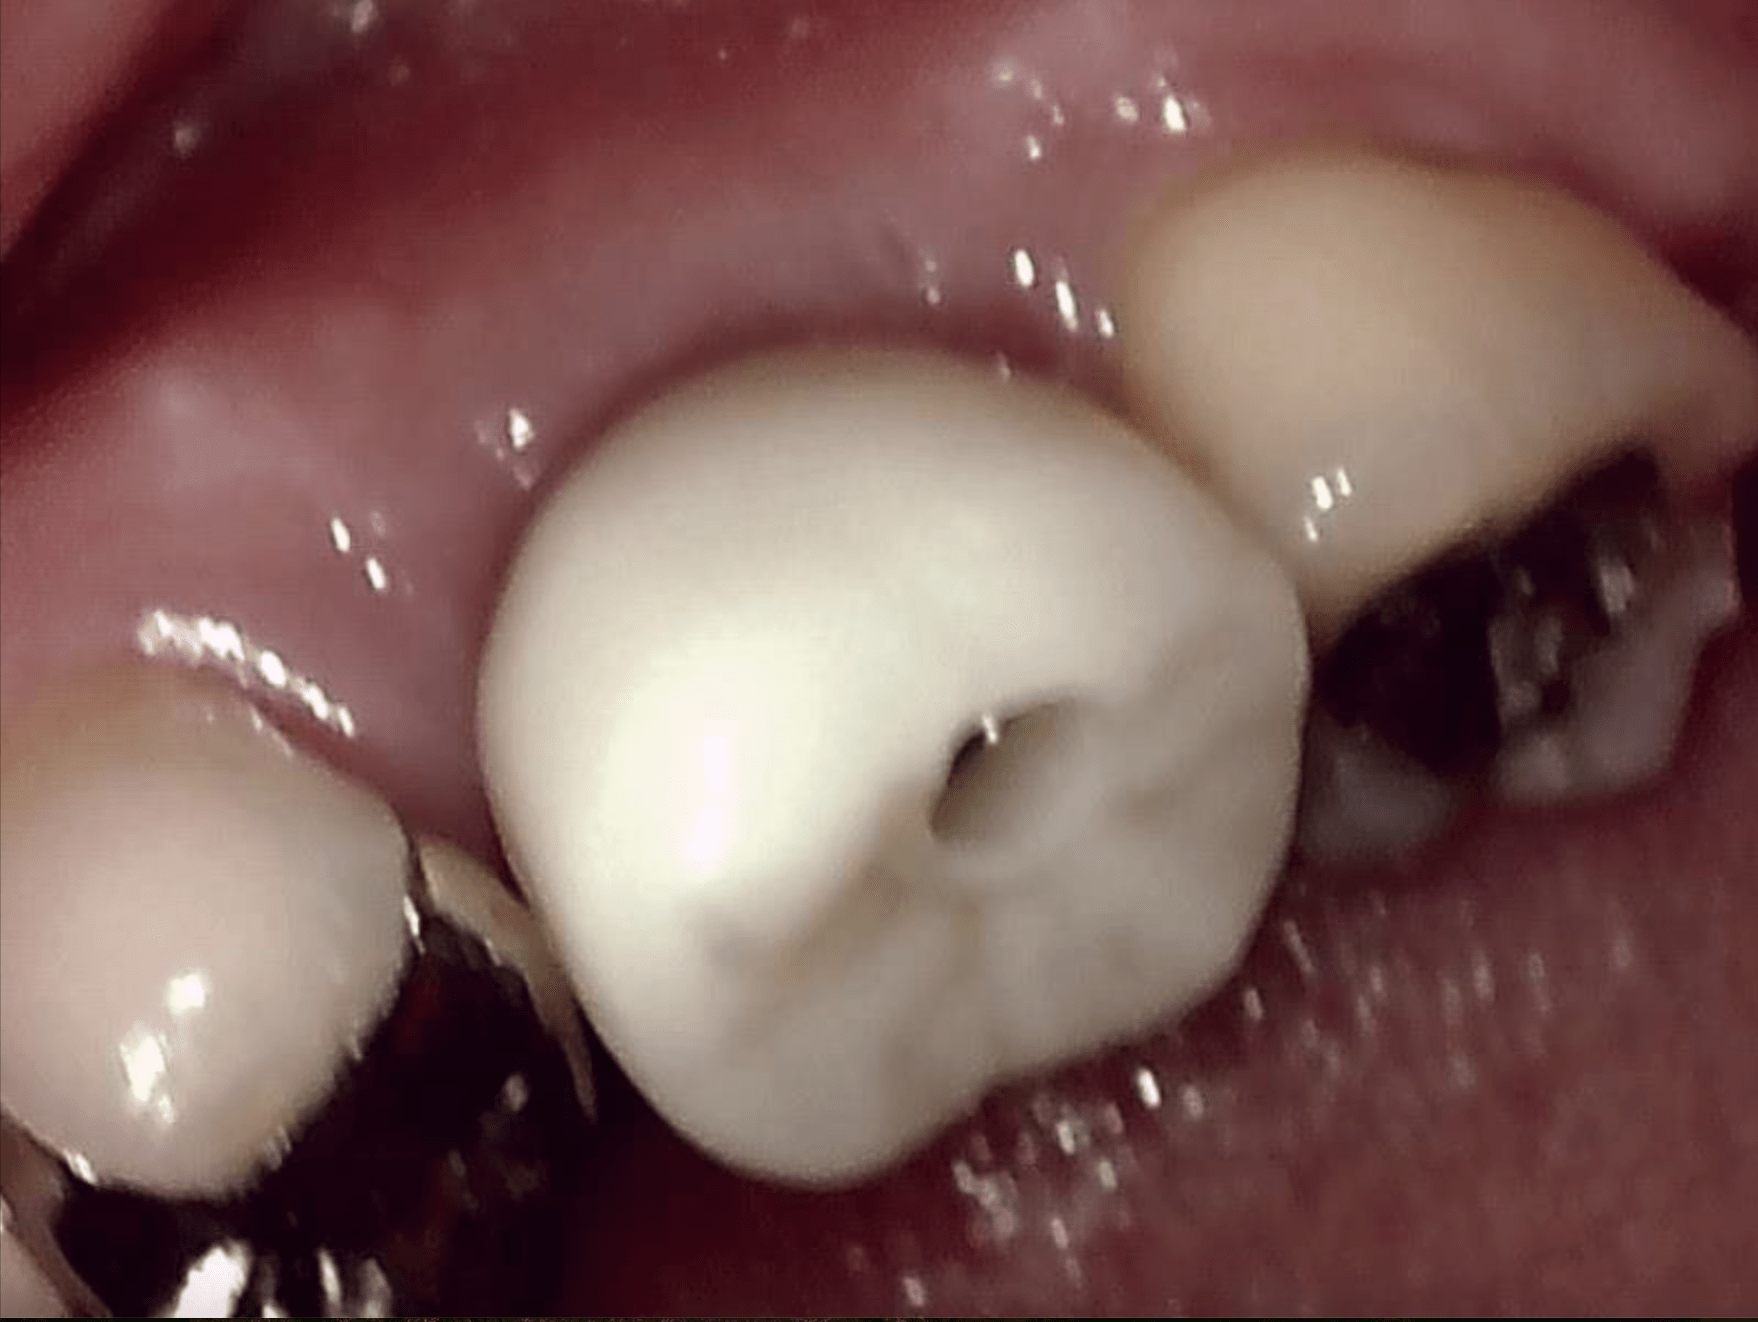

①コンタクト調整がしやすい、咬合調整もしやすい

②上部構造装着の診療時間の短縮が出来る

③ジルコニアに盛り足しが必要な場合は盛り足し対応ができる

等のメリットがあり、今後もこの方法で行こうと思っております。

患者様はアクセスホールといいまして、歯の穴はどうするの?とお思いかもしれませんが、CRという白くて硬い樹脂で

封鎖をします。それで問題なく、咬合できますし、何かあった時に外して、消毒したりすることができるのです。